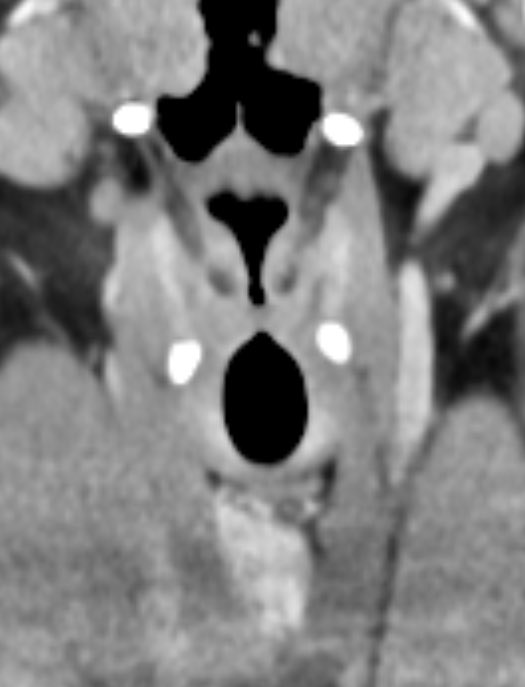

3️⃣Oligodendroglioma

▶️Cortically based mass mainly in ADULTS

▶️Location: FRONTAL and temporal lobes most common

Imaging:

▶️Classically presents as a gyriform cortical/subcortical based mass with GYRIFORM OR CLUMPED CALCIFICATIONS

▶️Consider this diagnosis in an ADULT WITH A CALCIFIED FRONTAL MASS ImageImageImageImage